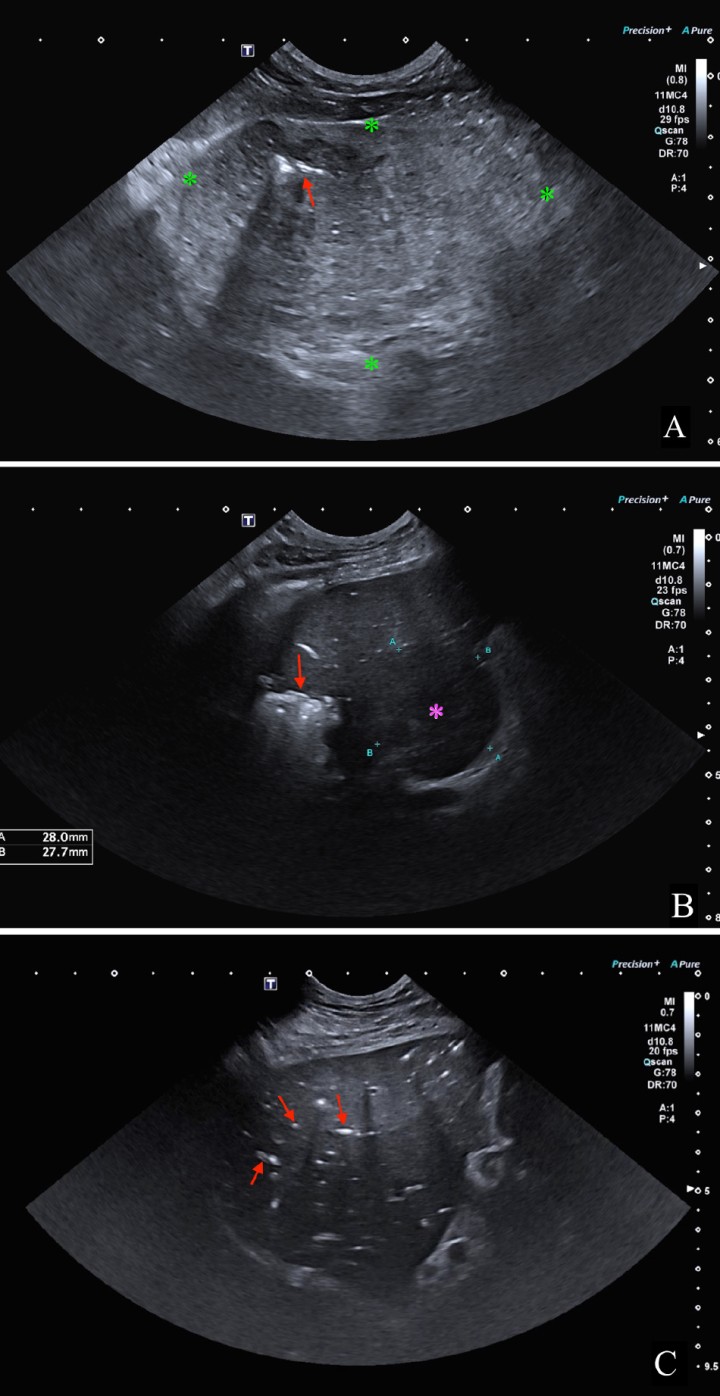

En el presente caso, se realizó una ecografía abdominal donde se identificó la presencia de una masa hepática, heterogénea y de bordes poco definidos, de 8,2 x 6,1 cm, localizada en el aspecto ventral derecho y medio del hígado, con mineralizaciones diminutas y presencia de focos ecogénicos que provocaban artefacto de reverberación compatible con gas intralesional (Fig. 3A); así como otro nódulo hipoecoico de 2,8 x 2,7 cm (Fig. 3B). Además, en el aspecto craneal de los lóbulos hepáticos derechos, se encontró una lesión cavitada, con gas en su interior (Fig. 3B) y múltiples acúmulos de gas intravascular adyacentes a la lesión (Fig. 3C). También se observó un pequeño volumen de líquido libre ecogénico entre los órganos abdominales, gas libre y reacción peritoneal adyacente al hígado.

<p>Imágenes ecográficas del parénquima hepático mostrando diferentes lesiones. (<strong>A</strong>) Se observa una masa hepática (*) con presencia de gas intralesional (flecha roja). (<strong>B</strong>) Lesión hepática con gas en su interior que produce artefacto de reverberación (flecha roja) y un nódulo hipoecoico y bien delimitado (*). (<strong>C</strong>) Se aprecian múltiples acúmulos de gas intraparenquimatosos a nivel intravascular (flechas rojas).</p>

Imágenes ecográficas del parénquima hepático mostrando diferentes lesiones. (A) Se observa una masa hepática (*) con presencia de gas intralesional (flecha roja). (B) Lesión hepática con gas en su interior que produce artefacto de reverberación (flecha roja) y un nódulo hipoecoico y bien delimitado (*). (C) Se aprecian múltiples acúmulos de gas intraparenquimatosos a nivel intravascular (flechas rojas).

Se realizó una abdominocentesis ecoguiada que confirmó una peritonitis séptica. Con estos hallazgos, el diagnóstico presuntivo fue de dos abscesos asociados a masas hepáticas con posible rotura, peritonitis y neumoperitoneo, así como hepatitis enfisematosa concurrente.

En los estudios ecográficos, los abscesos hepáticos presentan una apariencia variable según su duración. Generalmente, los abscesos hepáticos suelen mostrar una pared ecogénica con una parte central anecoica o hipoecoica. Si estos contienen gas, se identificará artefacto de reverberación en su interior.[ Larson MM. Liver and spleen. En: Thrall DE, 7th ed. Textbook of Veterinary Diagnostic Radiology. St. Louis, MO: Elsevier; 2018; 792-822 ] Dichos hallazgos han sido previamente descritos en el caso clínico presentado.